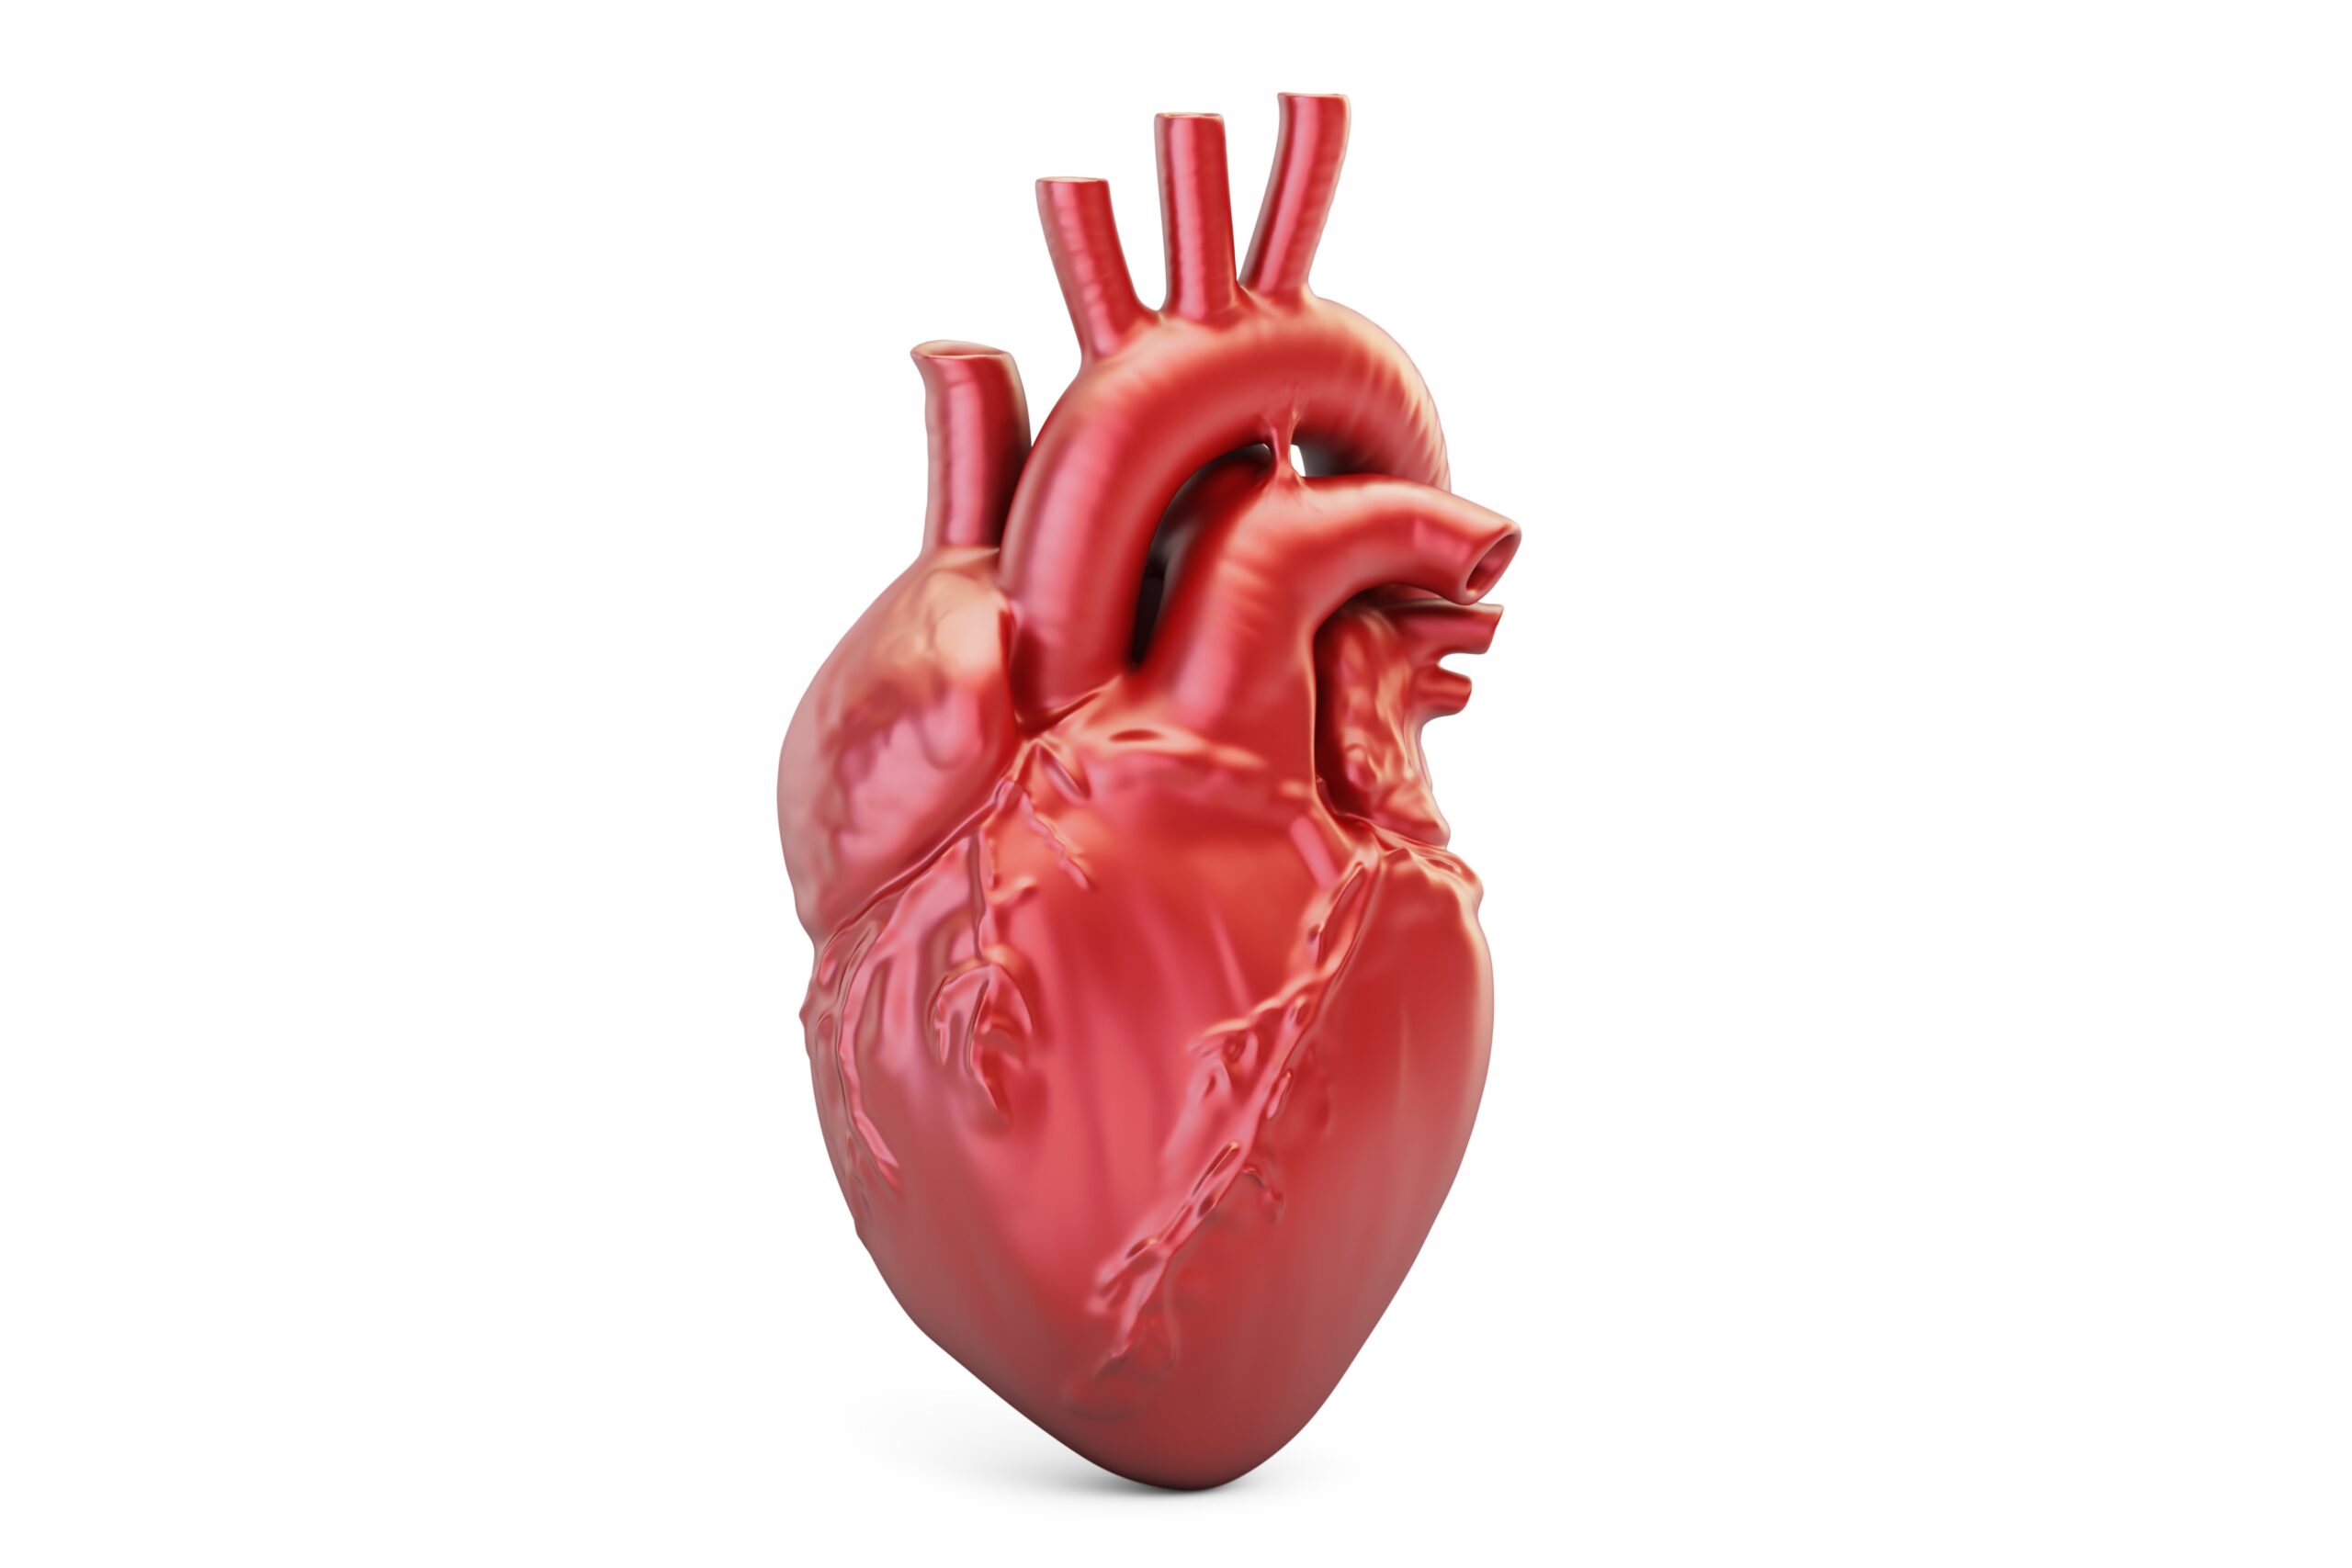

ضربان قلب نرمال برای سنین مختلف چقدر است؟

ضربان قلب چیست و انواع آن

به تعداد تپشهای قلب در یک دقیقه «ضربان قلب» میگویند. قلب یک اندام عضلانی است که در مرکز قفسه سینه قرار دار...

سندروم قلب شکسته چیست و چه علائمی دارد؟

کاردیومیوپاتی تاکوتسوبو (Takotsubo cardiomyopathy)، که برخی افراد به آن "سندروم قلب شکسته" میگویند، یک بیماری ناگهانی قلبی است که ناشی...

تپش قلب چه زمانی خطرناک میشود و نیاز به پزشک دارد؟

آشنایی با علائم تپش قلب

آیا تپش قلب میتواند یک احساس موقتی باشد که موجب افزایش لحظهای ضربان قلب میشود و به سرعت تسکین مییابد؟ گاهی...

انواع صدای قلب که با گوشی پزشکی شنیده می شود

صداهایی که از قلب شنیده می شود

صدای قلب از دو نوع صدا تشکیل شده است: صدای سیستولیک (قابل سمع هنگام سیستول قلبی) و صدای دیاستولیک (قابل...